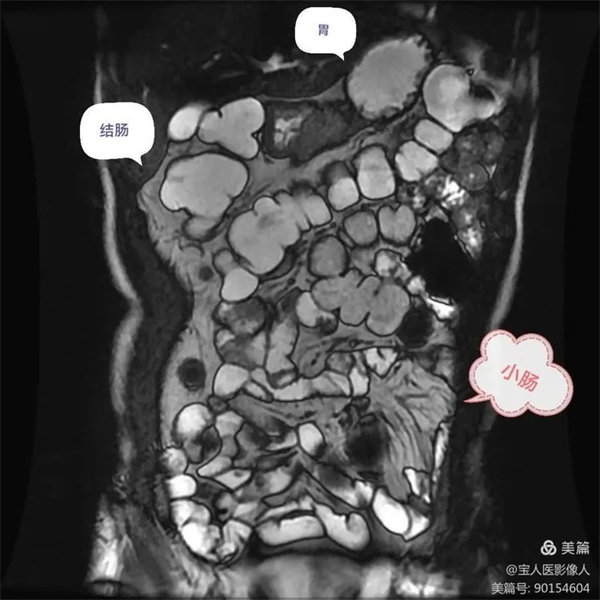

圖1,胃,小腸,結腸充盈顯示良好,局部小腸壁增厚,腸系膜病變組織包繞腸系膜動脈及分支血管塑形生長呈等T1,等T2信號腫塊。

圖6:胃,小腸充盈顯示良好,壁光滑,與周圍脂肪形成鮮明對比。

圖7:升、降結腸充盈顯示良好,結腸袋清楚,腸壁光滑,厚薄均勻,在腸液和周圍脂肪高信號之間對比鮮明。